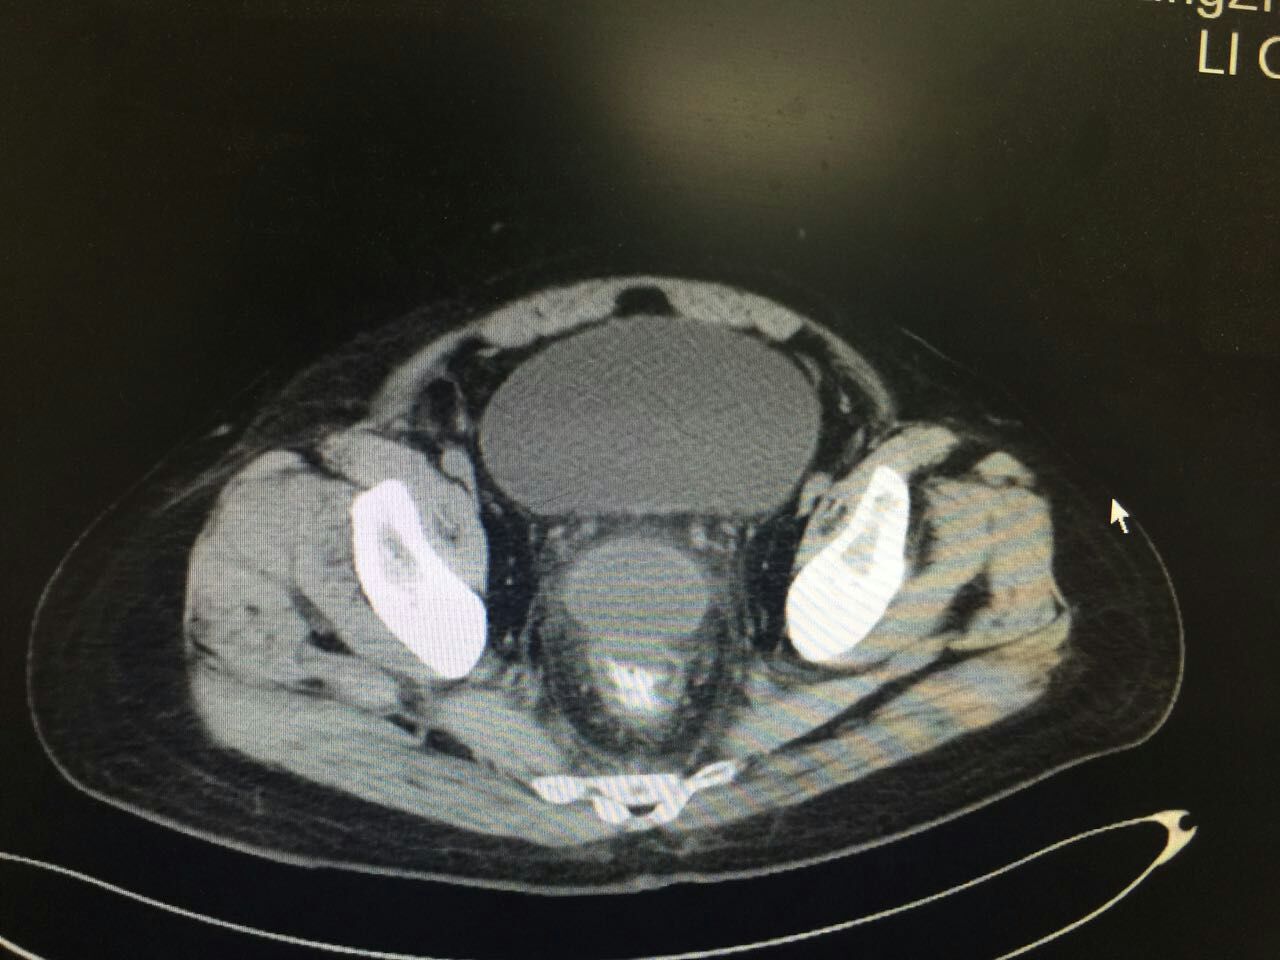

刘先生今年41岁,是一个公司的高管,三天前出现胃部不舒服,当时没有在意,几个小时以后出现了右下腹痛,当时去医院检查考虑是阑尾炎,医生建议他手术治疗。可是他因为工作忙没有答应,回去后自己输抗生素治疗,可是疼痛没有缓解还出现了发热,于是刘先生再次来到了医院,医生为他做了腹腔镜阑尾切除手术,手术中阑尾穿孔化脓,于是冲洗腹腔后放置了引流管,术后前三天刘先生恢复很好,排气,排便都很通常,也没有发热,引流管里液体不多,于是拔出了引流管,可是术后第五天患者出现了“里急后重”就是大便次数增多,几乎一个小时就要上一次厕所,还出现了发热,最高体温到了40℃,医生考虑盆腔脓肿刺激直肠造成的,于是做了CT检查,果真在直肠前方看到了一个脓肿,于是医生给刘先生做了经过直肠的脓肿穿刺引流,穿刺以后刘先生的体温下来了,大便的次数也减少了。

腹腔脓肿是阑尾切除术后的一个并发症,可以出现在肠壁之间,也可以出现在膈下,盆腔,而盆腔脓肿比较多见,因为一般来说盆腔是人体盆腔的最低点,就是说重力作用下脏东西会聚集到盆腔。阑尾炎合并穿孔腹腔就会出现细菌,甚至是粪石,在手术过程中虽然冲洗腹腔但是要想完全清洗干净比较困难,所以一般来说腹腔会残留细菌,但是多半会通过引流管引流出来,或者人体吸收,但是也有可能形成包裹性脓液,这样就会出现引流和吸收困难。